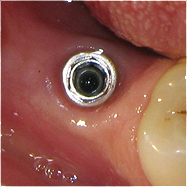

Resultado de colocação de implante dentário na Clínica São Filinto

O implante dentário é colocado no osso, através de uma pequena incisão na gengiva. É utilizada anestesia local, para que não sinta dor nem desconforto durante a cirurgia.

São realizados exames complementares de diagnóstico, nomeadamente radiografia panorâmica dos maxilares (ortopantomografia) e TAC (tomografia axial computorizada) - quando necessário -, por forma a selecionarmos quais os melhores implantes dentários a utilizar. A escolha da melhor solução para um implante dentário depende, essencialmente, da qualidade e da quantidade de osso disponível.